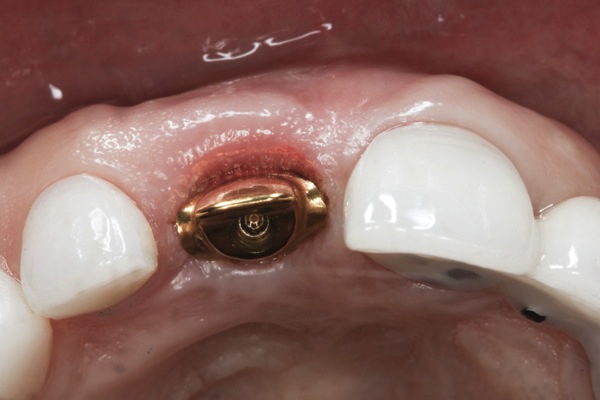

A 63-year-old female patient presented with mobility of her right maxillary incisor, tooth No. 8, secondary to endodontic therapy (Figure 1). Her medical and dental histories were non-contributory. Clinical and radiographic evaluations revealed an 8-mm probing depth on the palatal aspect. The tooth was deemed to be fractured (Figure 2). The treatment plan accepted by the patient was for extraction, immediate implant placement, and immediate provisional restoration, if possible.

Fig 1. Preoperative clinical photograph of fractured maxillary right central incisor (tooth No. 8).

Figure 1

Fig 16. Try-in of the definitive titanium-nitride–coated abutment.

Figure 16